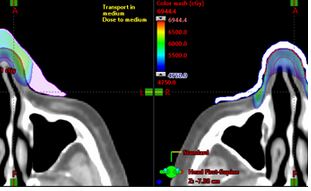

This patient case demonstrates the clinical application of Adaptiiv’s technology used in radiation oncology through the design and fabrication of both modulated and uniform thickness (simple) bolus.

This case is a great example of how Adaptiiv’s software can be effectively used for unique external beam electron treatments to significantly improve a patient’s treatment plan through accurate dose delivery, better target conformity and PTV coverage while reducing dose spill, hot spots, and air gaps.